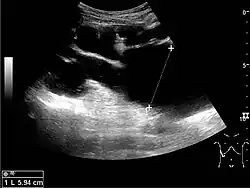

Cortical thickness should be estimated from the base of the pyramid and is generally 7–10 mm. If the pyramids are difficult to differentiate, the parenchymal thickness can be measured instead and should be 15–20 mm (Figure 3). The echogenicity of the cortex decreases with age and is less echogenic than or equal to the liver and spleen at the same depth in individuals older than six months. In neonates and children up to six months of age, the cortex is more echogenic than the liver and spleen when compared at the same depth.[1]

Figure 3. Measures of the kidney. L = length. P = parenchymal thickness. C = cortical thickness.[1]